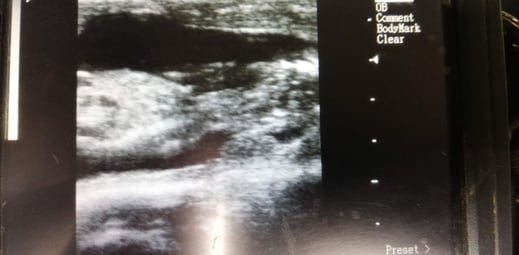

Gestation de 3 mois. La tête est à droite sur la photo. Vue dorsale.

Gestation de 6 semaines chez une vache. En noir, c'est le liquide amniotique dans lequel baigne le veau.Le cordon ombilical relie le veau au placenta.